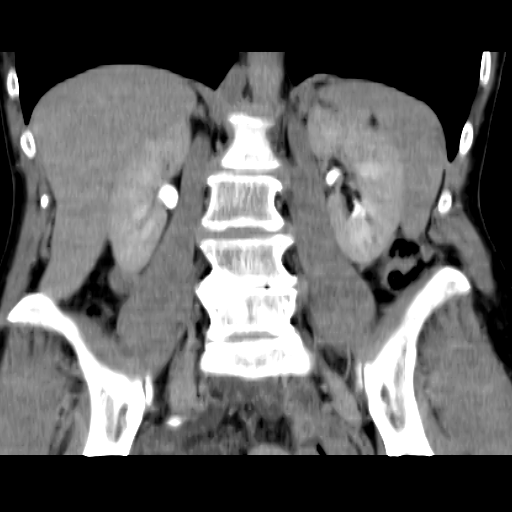

Обнаружилось небольшое образование низкой плотности, с достаточно ровными, четкими контурами парааортально справа около ножки диафрагмы на уровне тела L1 позвонка.

При нативе плотность 6HU, паренхиматозная - 18-20HU, экскреторная (15 минут) - 60-65HU.

Выкладываю по очереди срезы на одинаковых уровнях, сначала паренхиматозная, потом отсроченная фазы.